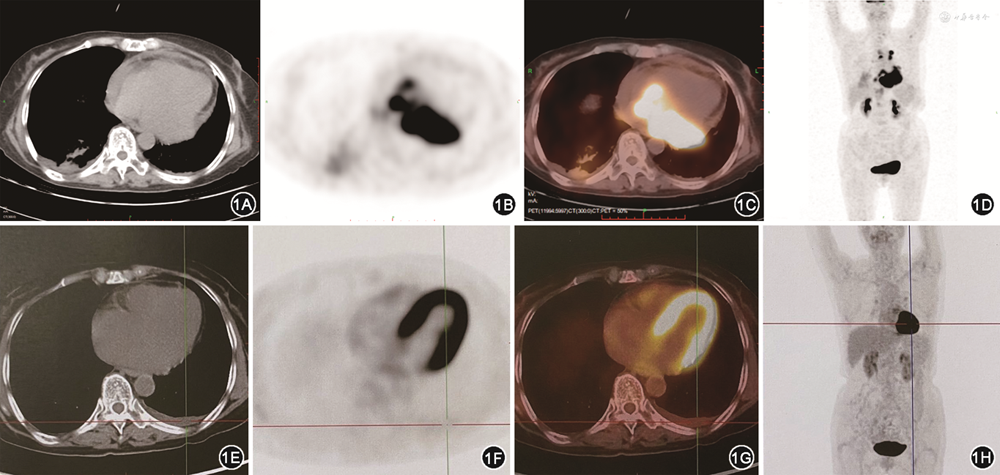

入院检查:白细胞计数8.8×109/L(参考值3.5~9.5×109/L),中性粒细胞百分比81.7%(参考值40.0%~75.0%),血红蛋白138 g/L(参考值115~150 g/L),血小板计数158×109/L(参考值125~350×109/L),肝肾功能正常,乳酸脱氢酶554 U/L(参考值109~245 U/L),糖类抗原(CA)125 156.6 U/ml(参考值0~30.2 U/ml),铁蛋白420 μg/L(参考值10~291 μg/L),β2微球蛋白4 252 μg/L(参考值651~2 295 μg/L)。心电图示窦性心动过速,肢体导联低电压。超声心动图示右心房内不规则大团块,分界欠清,累及左心房室沟(肿瘤可能),大量心包积液。正电子发射计算机断层显像(PET-CT)示左、右心房内巨大软组织肿块(约9.2 cm×5.3 cm),纵隔内、膈肌脚后间隙内及左上臂肌间隙内淋巴结氟-18-脱氧葡萄糖(18F-FDG)摄取异常增高(图1A~D)。心脏磁共振示左心房及右心房下壁、左心室侧壁、下壁基底段及中段占位,侵犯心肌、二尖瓣后叶及心包膜,考虑转移瘤或血管肉瘤可能。行心包穿刺引流、胸腔穿刺引流等缓解胸闷症状。脱落细胞学发现异型细胞,流式细胞分析示异常单克隆B淋巴细胞,考虑淋巴瘤可能。

患者转入血液科,骨髓活检未见异常细胞浸润。诊断为DLBCL(非生发中心型)Ⅱ期伴大包块,淋巴瘤国际预后评分3分,中高危。2020年11月23日起予2次利妥昔单抗单药治疗,2次R2方案(利妥昔单抗+来那度胺)化疗,1次R-miniCHOP方案(利妥昔单抗+环磷酰胺+多柔比星+长春地辛+泼尼松)及5次R2-miniCHOP方案(利妥昔单抗+来那度胺+环磷酰胺+多柔比星+长春地辛+泼尼松)化疗。患者呼吸困难明显好转,化疗5个月后复查PET-CT显示双侧心房内肿块消失,全身未见FDG异常高代谢灶(图1E~H)。随访至今患者状态良好,超声心动图未见心内占位。